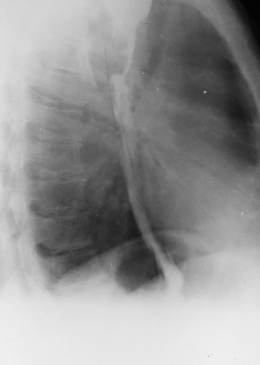

Pneumoperitoneu